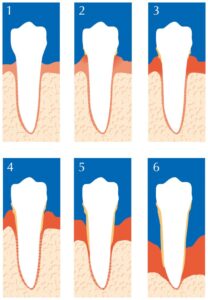

The stages og periodontal disease

Normal, healthy teeth are anchored to the bone and gum by fibers. There is a normal but narrow space around each tooth known as the sulcus (around 1-3 mm).

Gingivitis: The mildest form – The early stage – Bacterial deposits build up on the tooth surface causing irritation to the gum and periodontal ligament fibers. Gums become red, swollen and bleed easily. There is usually little or no discomfort. Gingivitis is reversible with professional treatment and optimal home oral care. Pockets are about 1-4 mm.

Mild Periodontitis: When gingivitis is untreated, the breakdown of supporting bone and tissue proceeds, the space around the tooth deepens. The sulcus is now called a pocket. The depth of the pocket is measured carefully, and provides information as to the stage of the disease. (“Mild” 1-2 mm loss of attaching fibers and bone – called Clinical Attachment Loss – Usually seen with 5 mm pockets).

Moderate to advanced Periodontitis: The plaque and its byproducts attack further, causing more of the fibers and bone support to be lost. The tooth might loosen, and the root may become exposed and sensitive. Unless treated, the tooth may fall out or need to be removed. (“Moderate” 3-4 mm or “Advanced” 5 mm or higher Clinical Attachment Loss – Usually seen with 6 mm pockets or higher).